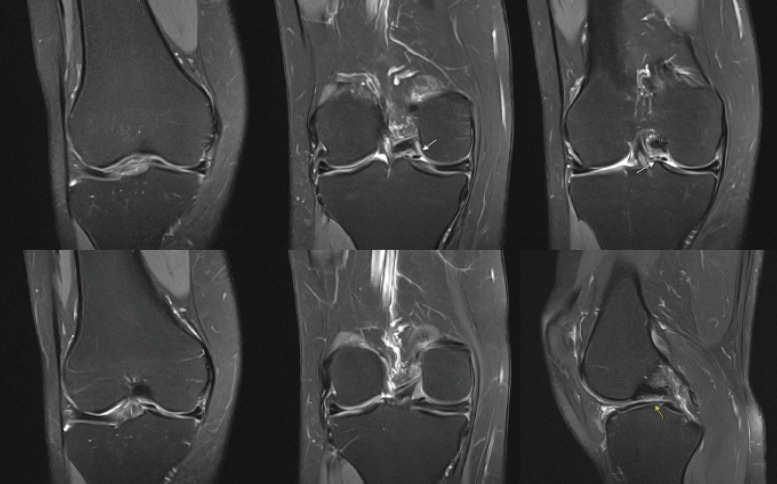

Case report: Our patient is a 38-year-old female who presented to the outpatient orthopedic clinic complaining of right knee pain in the setting of a traumatic kneeling event. She had a past medical history of asthma, polycystic ovary syndrome, and anxiety, but no surgical history related to the knee. She underwent magnetic resonance imaging identified what appeared to be a bucket-handle medial meniscus tear. The patient was brought to the operating room where diagnostic arthroscopy revealed a radial tear at the posterior horn of the medial meniscus as well as an anomalous connection between the anterior and posterior roots. The band specifically ran from the posterior horn of the medial meniscus, then superiorly and along the posterior cruciate ligament, and ultimately attached to the anterior horn of the medial meniscus in an "O" shape. In addition, a large patellofemoral plica was identified overlying the lateral femoral condyle. The tear, plica, and anomalous band were all debrided. The patient was progressing well on her most recent 7-month follow-up visit.